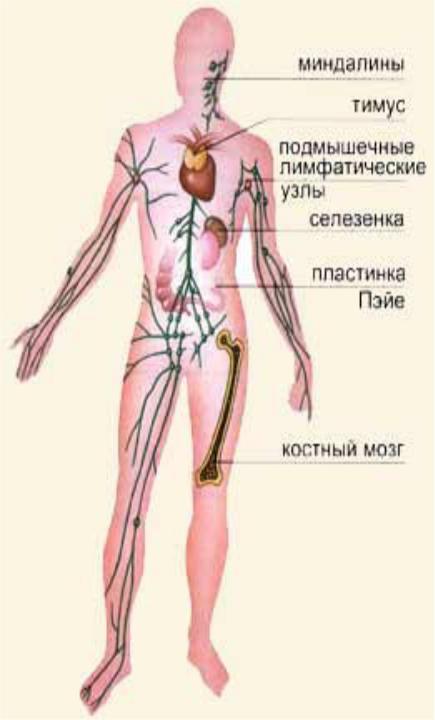

Изучение костного мозга: анатомия и функции

Раздел: Фотогалерея мыслей